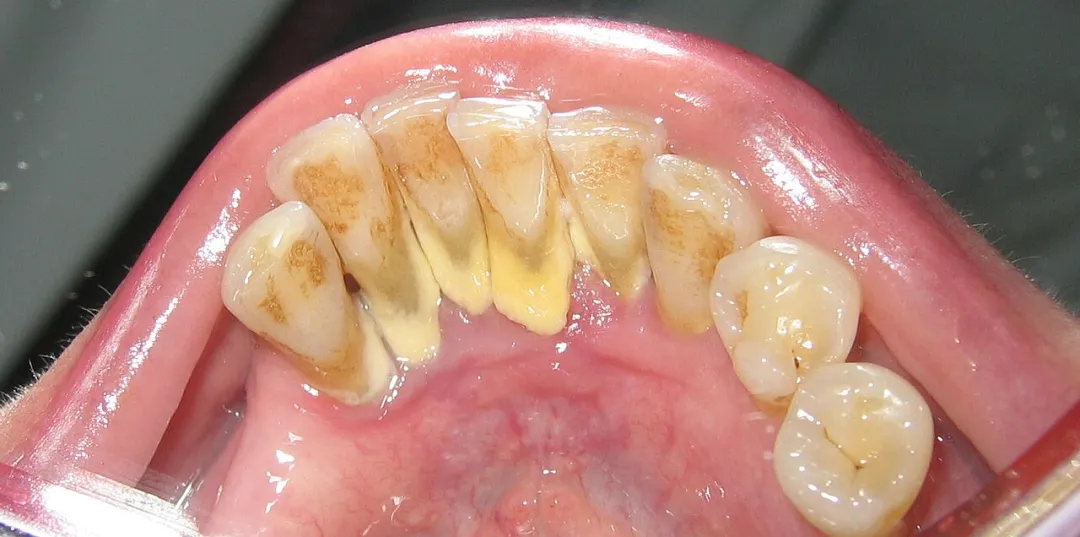

牙齿上的牙结石(牙根处黄色部分)

若牙菌斑未被彻底清除,就会越积越厚。同时,它会不断吸收唾液中的矿物质(尤其是钙、磷等元素),逐渐“石化”变硬。

严格来讲,这就是牙结石的雏形。刚开始形成时,它比较松散柔软,可通过认真刷牙、使用牙线清除。

但一旦完全钙化,就像给牙齿贴了层硬壳,普通牙刷难以将其去除。不过,牙结石也会脱落,当它不断增多,有些患者自称“牙齿碎了一块”,其实碎掉的就是牙结石,而掉落的只是一小部分。

这也解释了为何牙结石易出现在下门牙内侧、上后牙外侧,这些位置是唾液腺开口处,矿物质供应充足,是牙结石的“高发区”。

牙结石表面粗糙、多孔,是细菌的“理想栖息地”。它会吸附食物残渣,使细菌聚集,细菌分解蛋白质,释放出有臭鸡蛋气味的硫化物,即“口臭”。